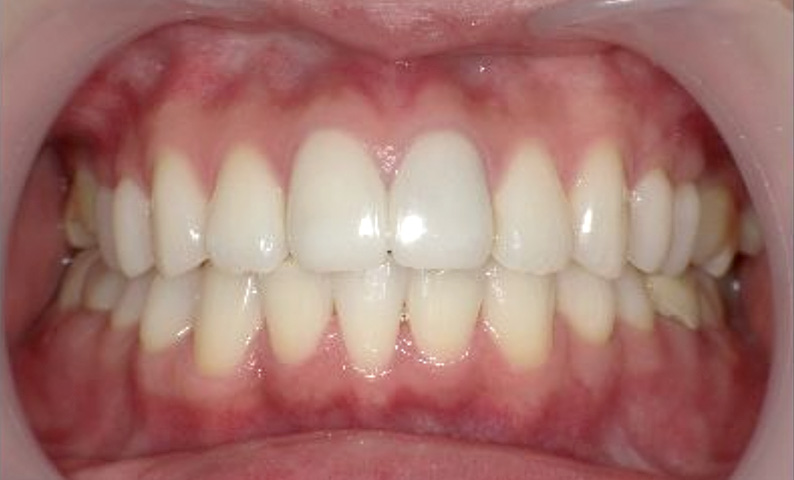

症例_025 上下顎の部分矯正

治療期間:13ヶ月金額:51万円+税女性前歯のガタガタ出っ歯

| Before | After |

|---|---|